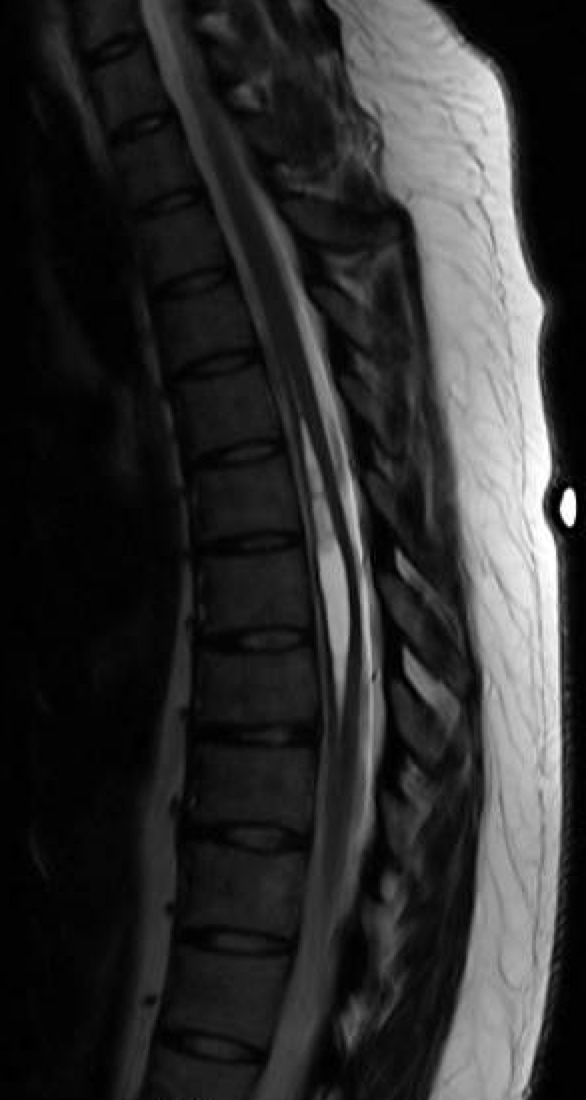

Syrinx of the thoracic spinal cord YouTube Syrinx Of Spinal Cord Physical Therapy 4 the fluid forms a cavity called a syrinx. The cyst, which is sometimes called a syrinx, can grow larger over. A case report suggests spinal cord stimulation may be effective for patients with syringomyelia related neuropathic pain 30. People with primary spinal syringomyelia and associated symptoms are often managed conservatively. The goal of surgery is to remove the pressure. Syrinx Of Spinal Cord Physical Therapy.